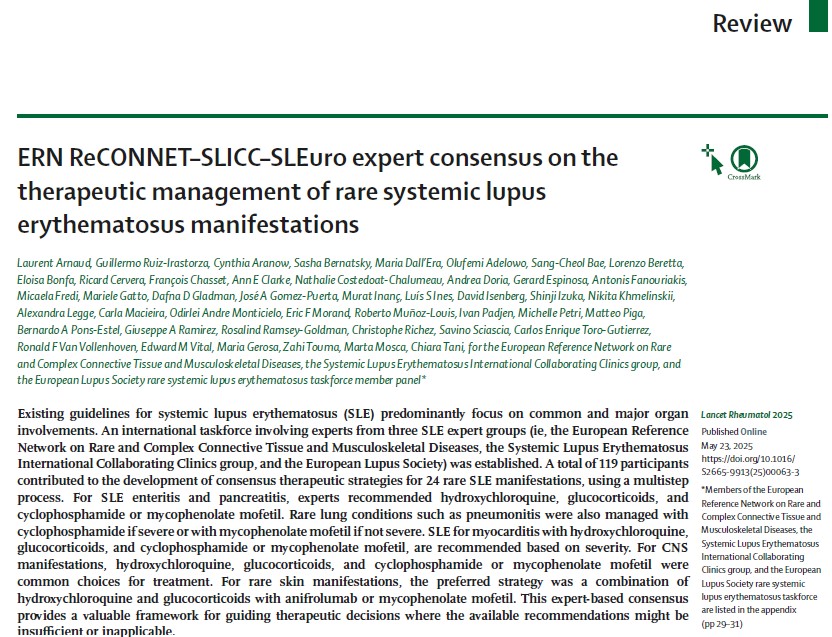

NEW for #LUPUS2025—ERN ReCONNET 🇪🇺–SLICC–SLEuro expert consensus on the therapeutic management of rare systemic #lupus erythematosus manifestations bit.ly/3YXEmAO Free to read with registration on lancet.com (also free) Laurent ARNAUD #SLE